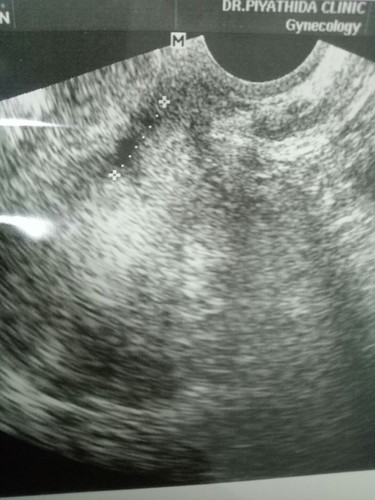

ท้อง6สัปดาห์มีเลือดออก เลยไปหาหมอคุณหมอซาวด์ทั้งหน้าท้องและทางช่องคลอดหมอบอกว่าถุงตั้งครรภ์ผิดรูป และคาดว่าอาจจะเป็นท้องลม เพราะไม่ได้ยินเสียงหัวใจเด็ก แต่หมอก็ยังพูดให้เรามีหวังขึ้นนิดนึงคือให้มาตรวจอีก2อาทิตย์เผื่อรอบนี้น้องมีการเจริญเติบโตแต่ถ้าไม่มีก็ยุติการตั้งครรภ์ แม่ๆท่านไหนเคยมีประสบการณ์แบบนี้บ้างคะท้องแรกปล่อยมีน้องมานานมากแล้วแต่พึ่งมีเลยกังวลไม่อยากเสียน้องไปค่ะ